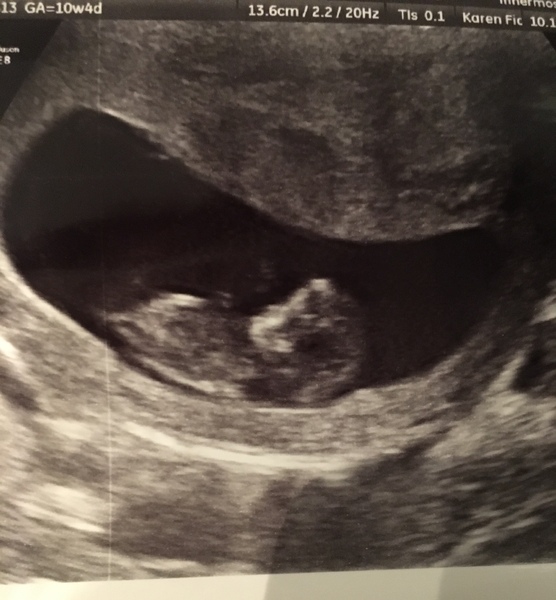

Myfirstbornisacollie · 10/11/2016 20:07

This evenings scan- lots of wriggling and arm flapping from active Bean!

Fab pic myfirst - not much of a bean anymore!!

Congrats myfirst Gorgeous pic!

Gorgeous pic myfirst how many weeks are you?

myfirst are we due date buddies? Nice scan pic Smile